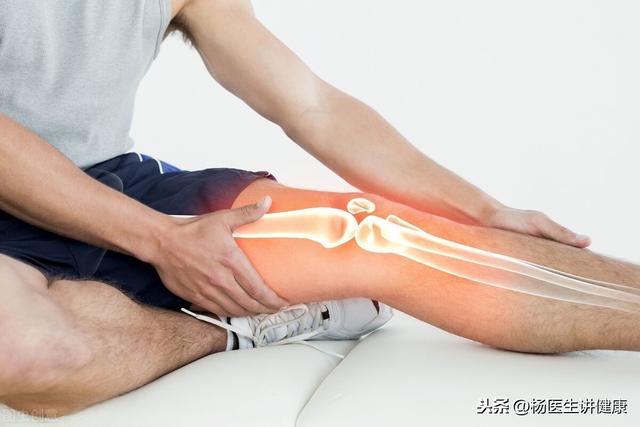

膝の冷えは実は本当によくあることで、多くの人がこのように感じている。40歳を超えると、このように感じる人がかなり増える。特に天候の変化があると、痛みを伴うケースもある。膝の関節を曲げ伸ばししたときに音が鳴る場合は、関節軟骨や軟部組織の問題の膝関節に見られることがほとんどである。

膝関節の曲げ伸ばしをするときにガラガラと音がする。雪を踏んでいるような、ガサガサという音がすることもある。関節の軟骨が滑らかでないのが主な原因だ。その理由は、私たちの自転車のベアリングにグリットが入っているのと同じで、とてもよく理解できる。

関節軟骨を損傷する原因は、体重過多、スポーツなどの単純な使いすぎ、外傷、関節リウマチ、痛風性関節炎、ごく一般的な変形性関節症などの軟骨びらんなど、実にたくさんある。

膝関節の骨の表面には、軟骨の層が付着しており、一般的に膝関節に過度の圧力負荷がかかると、軟骨の摩耗や破損のため、私たちの活動では、痛みを示すでしょう。軟骨の摩耗や破損が徐々に悪化し、太ももの骨とふくらはぎの骨の硬い衝突、関節の安定性の損失につながる、徐々に骨軟化症、血液循環の悪化があり、涼しさと破裂音は避けられない。